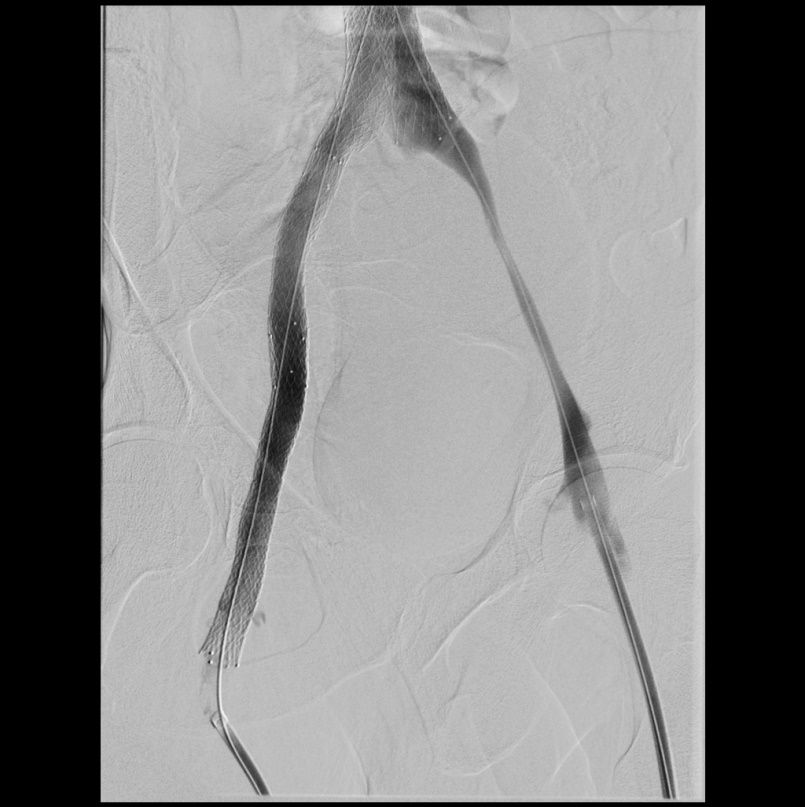

Beispiel eins Patienten mit Postthrombotischem Syndrom des rechten Beines (Schmerzen und Schwellung). Verschluss der Beckenvenen rechts (linkes Bild).

Rekanalisation mit Dilatation und Stents der rechtsseitigen Beckenvenen  (rechtes Bild). Hierdurch wieder freier Fluss in den Beckenvenen.